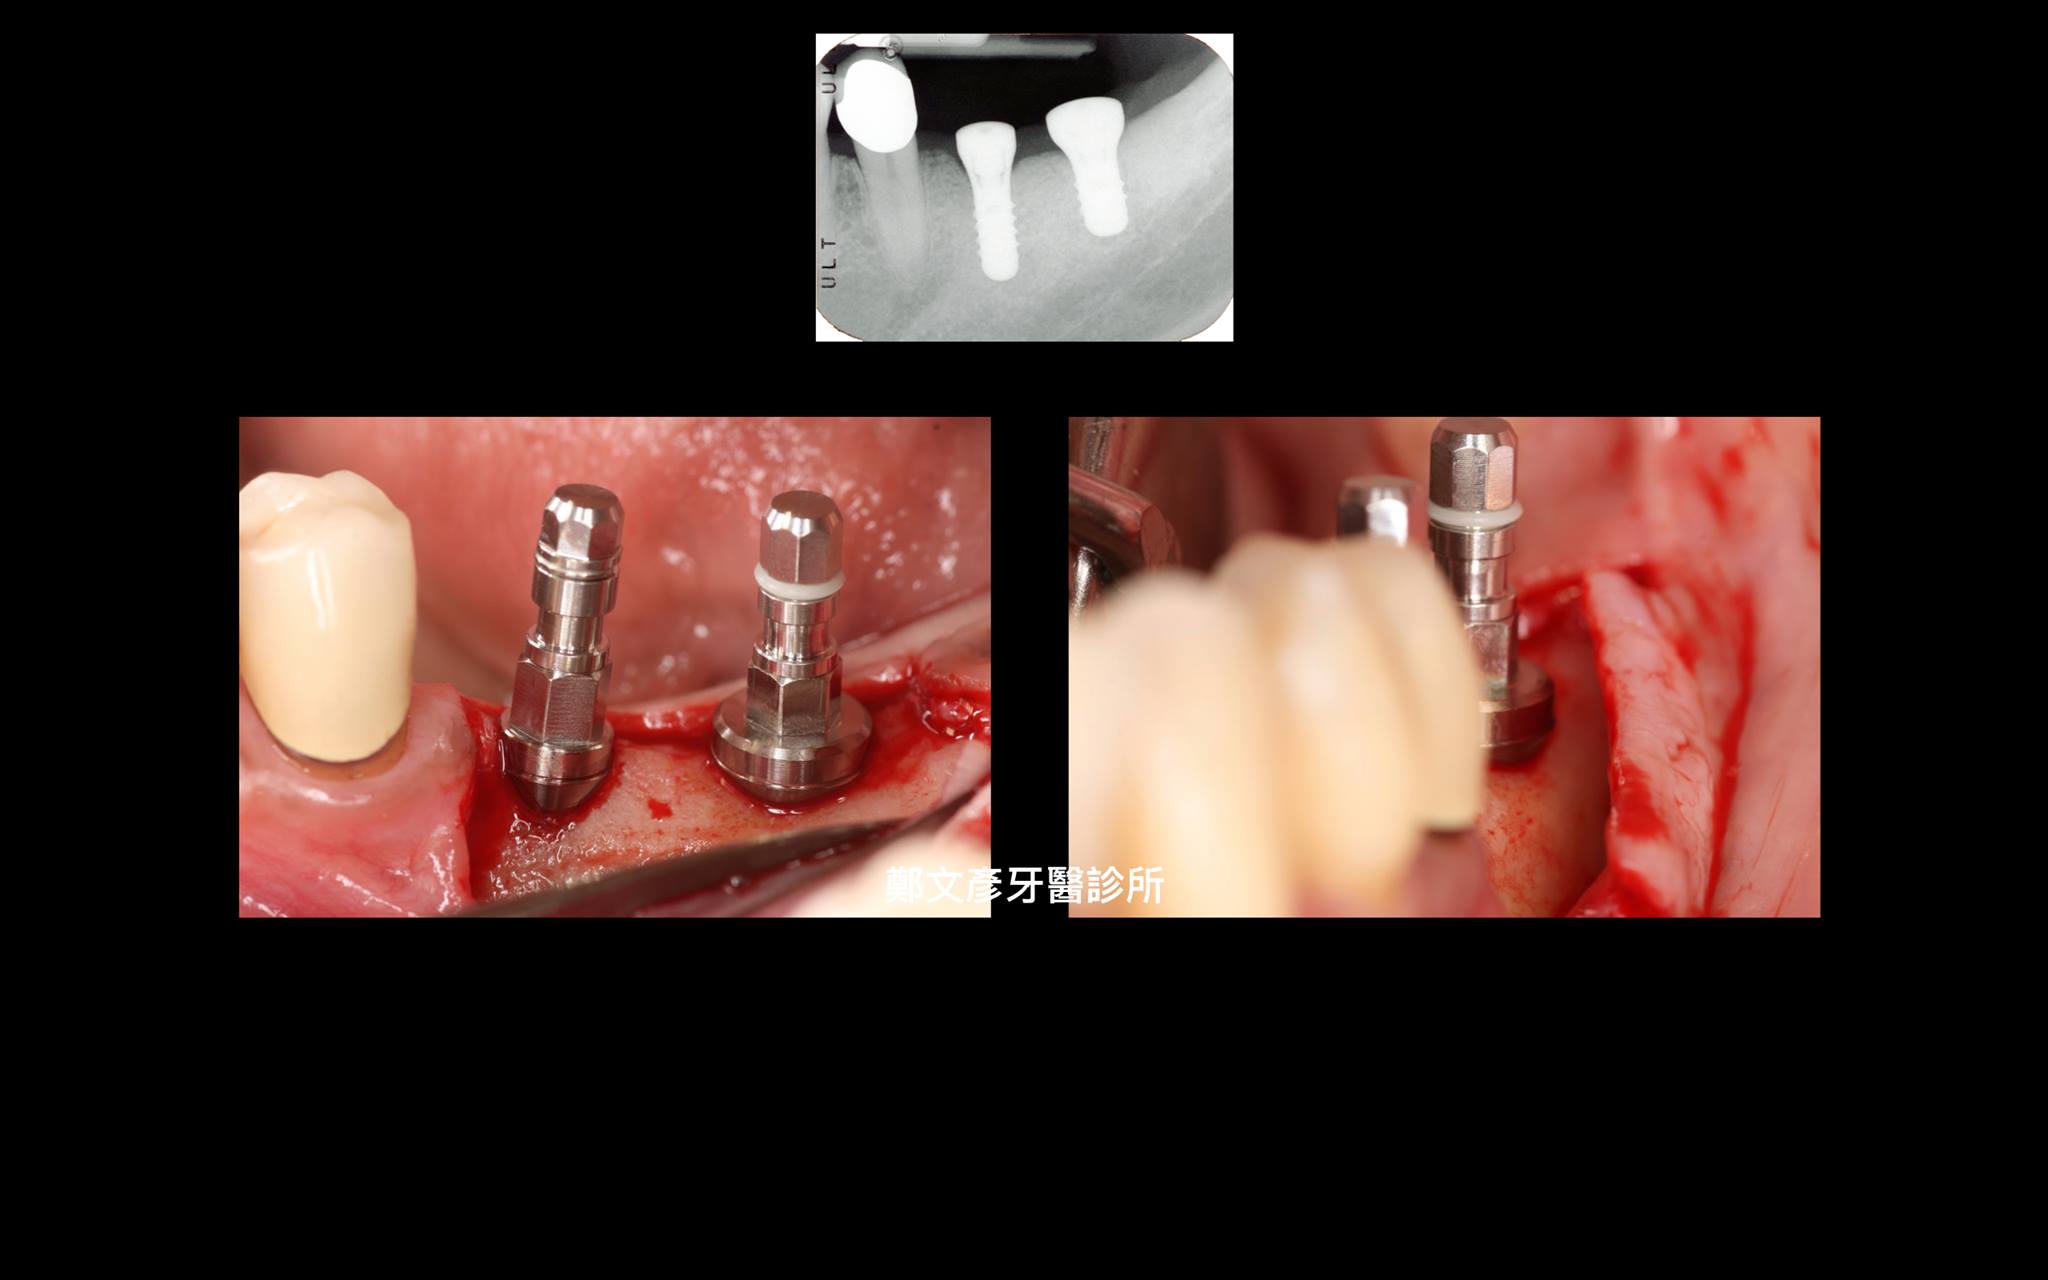

植牙美學(後牙區)

植牙美學